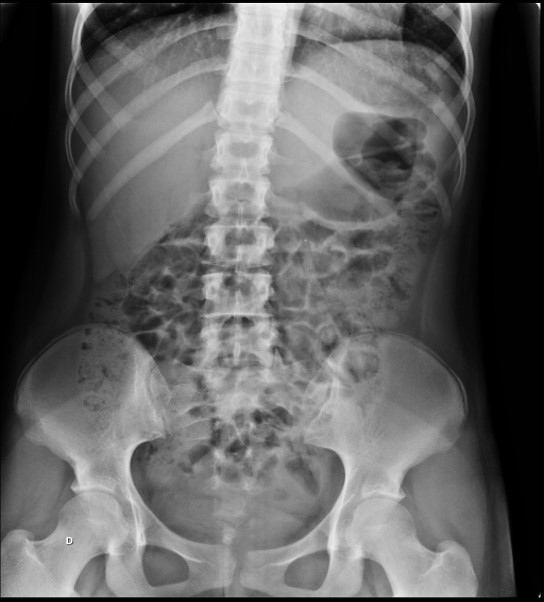

PCT COM GASES NO DELGADO DE FORMATO OVAL OU ESFÉRICO E GASES NO COLON E ESTÔMAGO LEMBRANDO TABULEIRO DE XADREZ. QUAL DIAGNÓSTICO?

Falso abdome agudo (Íleo Paralítico)